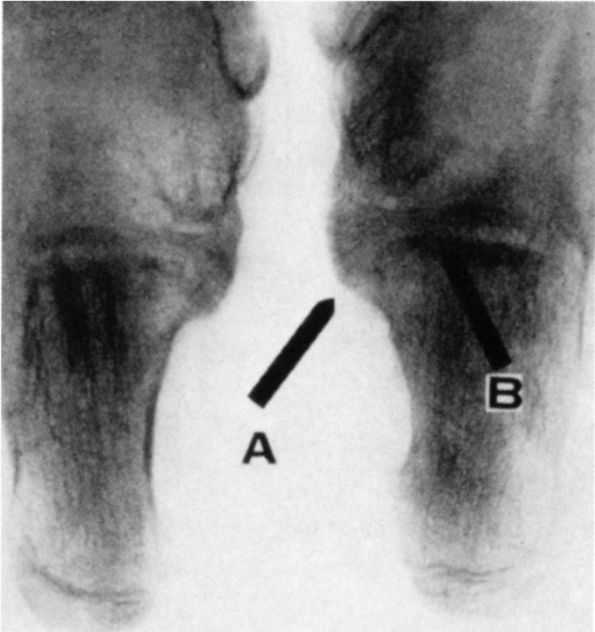

![]() |

FIGURE 20-21. Tarsal coalition. Note the position of the involved left foot with the forefoot in abduction (A) and heel in valgus (B). Also note the loss of the longitudinal arch.